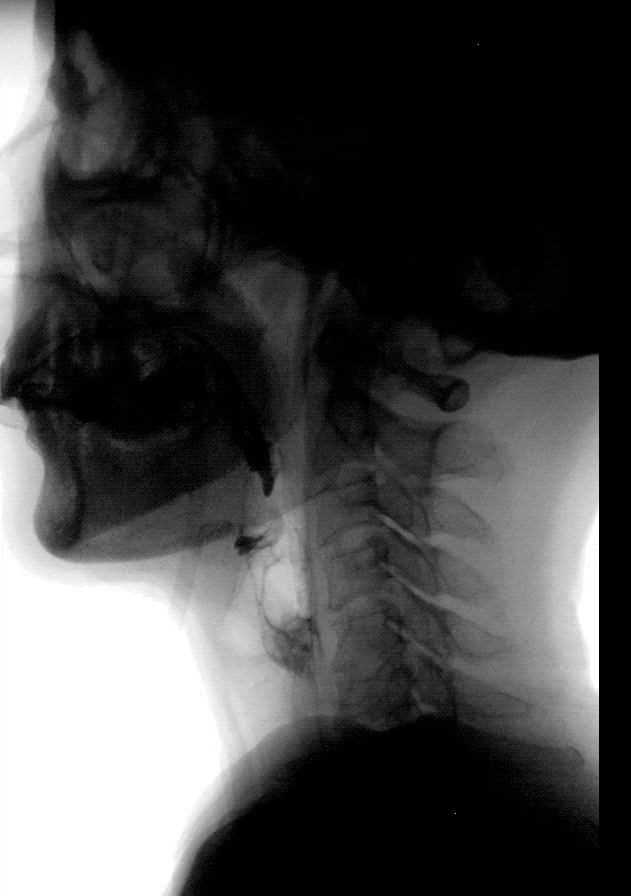

▲吞咽造影

吞咽造影检查(videofluoroscopic swallowing study, VFSS),一般由专业医师和言语治疗师共同合作完成,是目前国际上公认的吞咽功能评价的金标准。

在透视下观察吞咽不同体积和黏稠度的食团,提供吞咽相关结构的运动情况,确定患者有关误吸的危险因素,预防误吸的发生;明确是否需要改变进食方式,以改善营养状态。